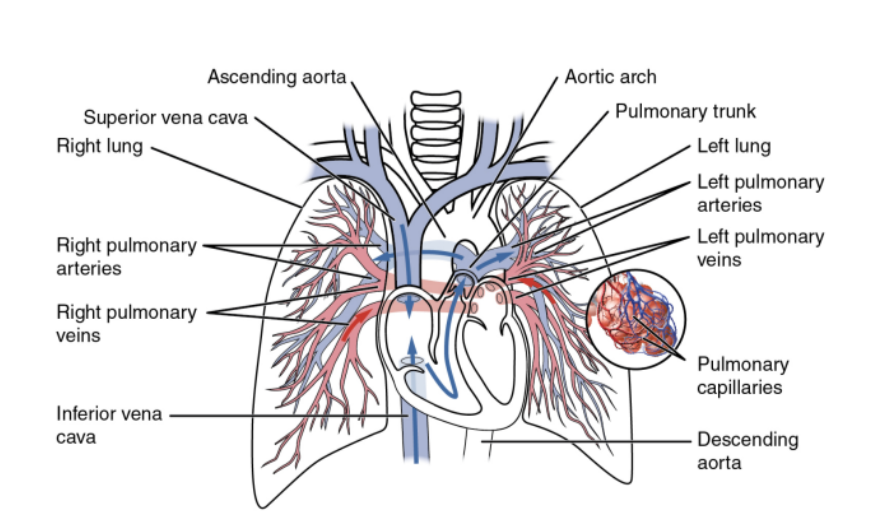

Overall vasculature of the lungs image

Pulmonary arteries (overall)

1 right, 1 left, originate from the pulmonary trunk & carry deoxygenated blood to the lungs from the right ventricle of the heart

Bifurcation of pulmonary trunk occurs to left of midline just inferior to vertebral level TIV/V, and anteroinferiorly to the left of the bifurcation of the trachea

Right vs left pulmonary arteries

Right pulmonary artery —

Slightly longer than left

Crosses horizontally at the mediastinum passes anteriorly & inferiorly to the bifurcation of the trachea, & anteriorly to the right main bronchus — also posteriorly to the ascending aorta, superior vena cava, and upper right pulmonary vein

Enters into root of lung giving off a large branch to the superior lobe of the lung

Main branch continues through hilum to give off a second recurrent branch to superior lobe before dividing to supply both the midline & inferior lobes

Left pulmonary artery —

Shorter than the right, anterior to the descending aorta & posterior to the superior pulmonary vein

Pulmonary veins —

On both sides — superior & inferior pulmonary vein

Carry oxygenated blood from lungs back to heart

Begin at hilum, pass through root of lung, & immediately drain into left atrium

Pulmonary circulation —

The movement of blood from the heart to the lungs for oxygenation, then back to the heart again — steps —

Blood enters the right atrium of the heart through the superior & inferior vena cavae

The right atrium contracts, thus pushing the blood through the tricuspid valve into the right ventricle

The right ventricle contracts, pushing the blood through the pulmonary valve & into the pulmonary artery

The pulmonary artery carries the deoxygenated blood to the lungs

Where it picks up O2 & releases CO2 via gas exchange

The oxygenated blood then travels back to the heart through the pulmonary veins to enter the left atrium

The left atrium contracts, pushing blood through the mitral valve & into the left ventricle

Left ventricle contracts, pushing oxygenated blood through aortic valve & into aorta

Aorta distributed oxygenated blood to remainder of body, delivering O2 & nutrients to the organs & tissues